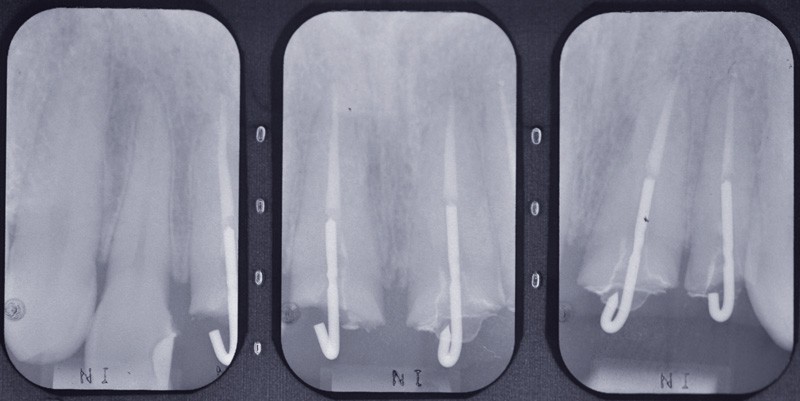

Dans un premier temps, sur la base d’un examen clinique et radiologique (fig. 2b), de modèles d’étude (si nécessaire montés sur simulateur), la conservation de piliers dentaires futurs, pulpés ou dépulpés, partiels ou périphériques, est évaluée, avec l’assistance possible de thérapeutiques orthodontiques et parodontales, avant le recours à des piliers implantaires.